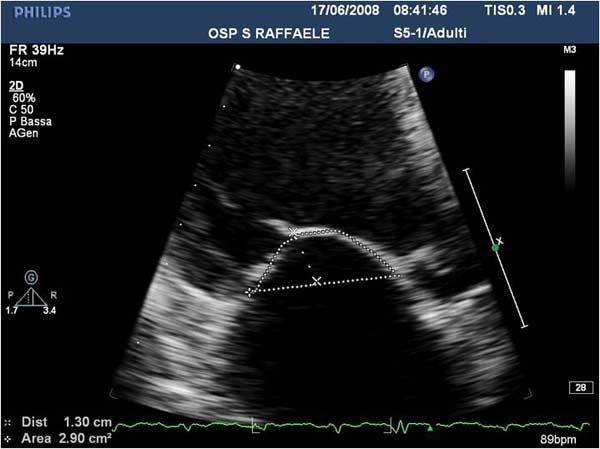

Figure 6

In absence of controlled clinical trial data which are forthcoming from the EVEREST II randomized study, the indications for the MitraClip therapy are currently based on registry experience and will evolve as the technique improves, experience is growing and the data to demonstrate efficacy and safety becomes available. At this time, the best indication for the MitraClip therapy is for symptomatic patients with clinically significant functional or degenerative MR who are at high or increased risk for open heart surgery. From a pure technical standpoint, the procedure so far has only been demonstrated in a subgroup of patients with specific anatomical characteristics which are summarized below and shown in Figure 3. Anatomic suitability is assessed by transesophageal echocardiography, and mitral regurgitation should originate from the central portion of the valve involving the A2-P2 segments, since the device is not ideal to work in the commissures at this time; the mechanism of MR can be either a prolapse/flail or MR due to restricted leaflet motion unrelated to rheumatic disease; the separation between the two leaflets at the site of regurgitation should be limited; severe annular dilatation and/or severe calcification should be absent or is relevant. In case of flail, the flail segment width should be less than 15 mm, and the flail gap less than 10 mm. Figure 4 is a 3D echo image of a patient with posterior leaflet prolapse selected for MitraClip therapy. In case of functional MR, the leaflets should have a minimal residual tissue available for coaptation with the MitraClip device. Figure 5 shows 2D color Doppler jet extension over the coaptation line at TEE short axis transgastric view, while Figure 6 shows the tenting area and the coaptation depth of a patient undergoing MitraClip implant.